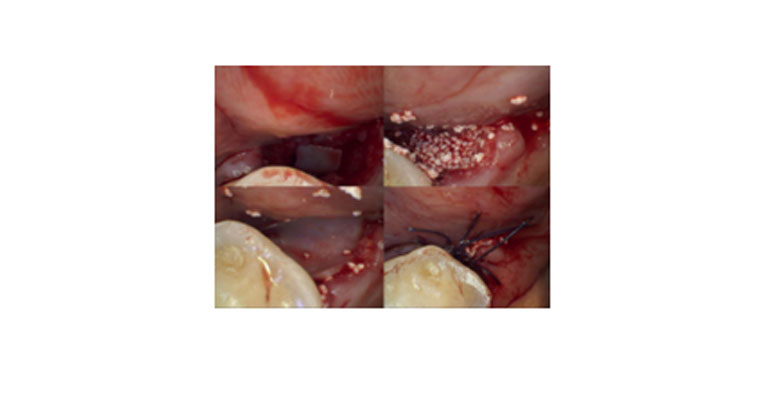

Surgical closure of oroantral openings is a meticulously planned and executed procedure within the domain of oral and maxillofacial surgery. It necessitates a thorough understanding of the anatomical and physiological aspects of the oral and maxillofacial region. The closure of these openings involves a multi-faceted approach, which includes meticulous soft tissue management, bone grafting, and an appreciation of sinus pathology.

The surgical intervention typically commences with precise debridement and disinfection of the affected area to mitigate the risk of infection. Depending on the size and location of the defect, various techniques may be employed for closure, such as buccal advancement flaps, palatal rotational flaps, and use of autogenous or allogeneic bone grafts to reestablish continuity in the maxillary bone.

A critical aspect of oroantral surgical closures is the management of the maxillary sinus. This entails careful assessment of sinus health, with attention to any existing sinus pathology that may need concurrent treatment. In cases where the maxillary sinus is compromised, additional procedures, such as sinus augmentation, may be warranted to optimize functional and aesthetic outcomes.